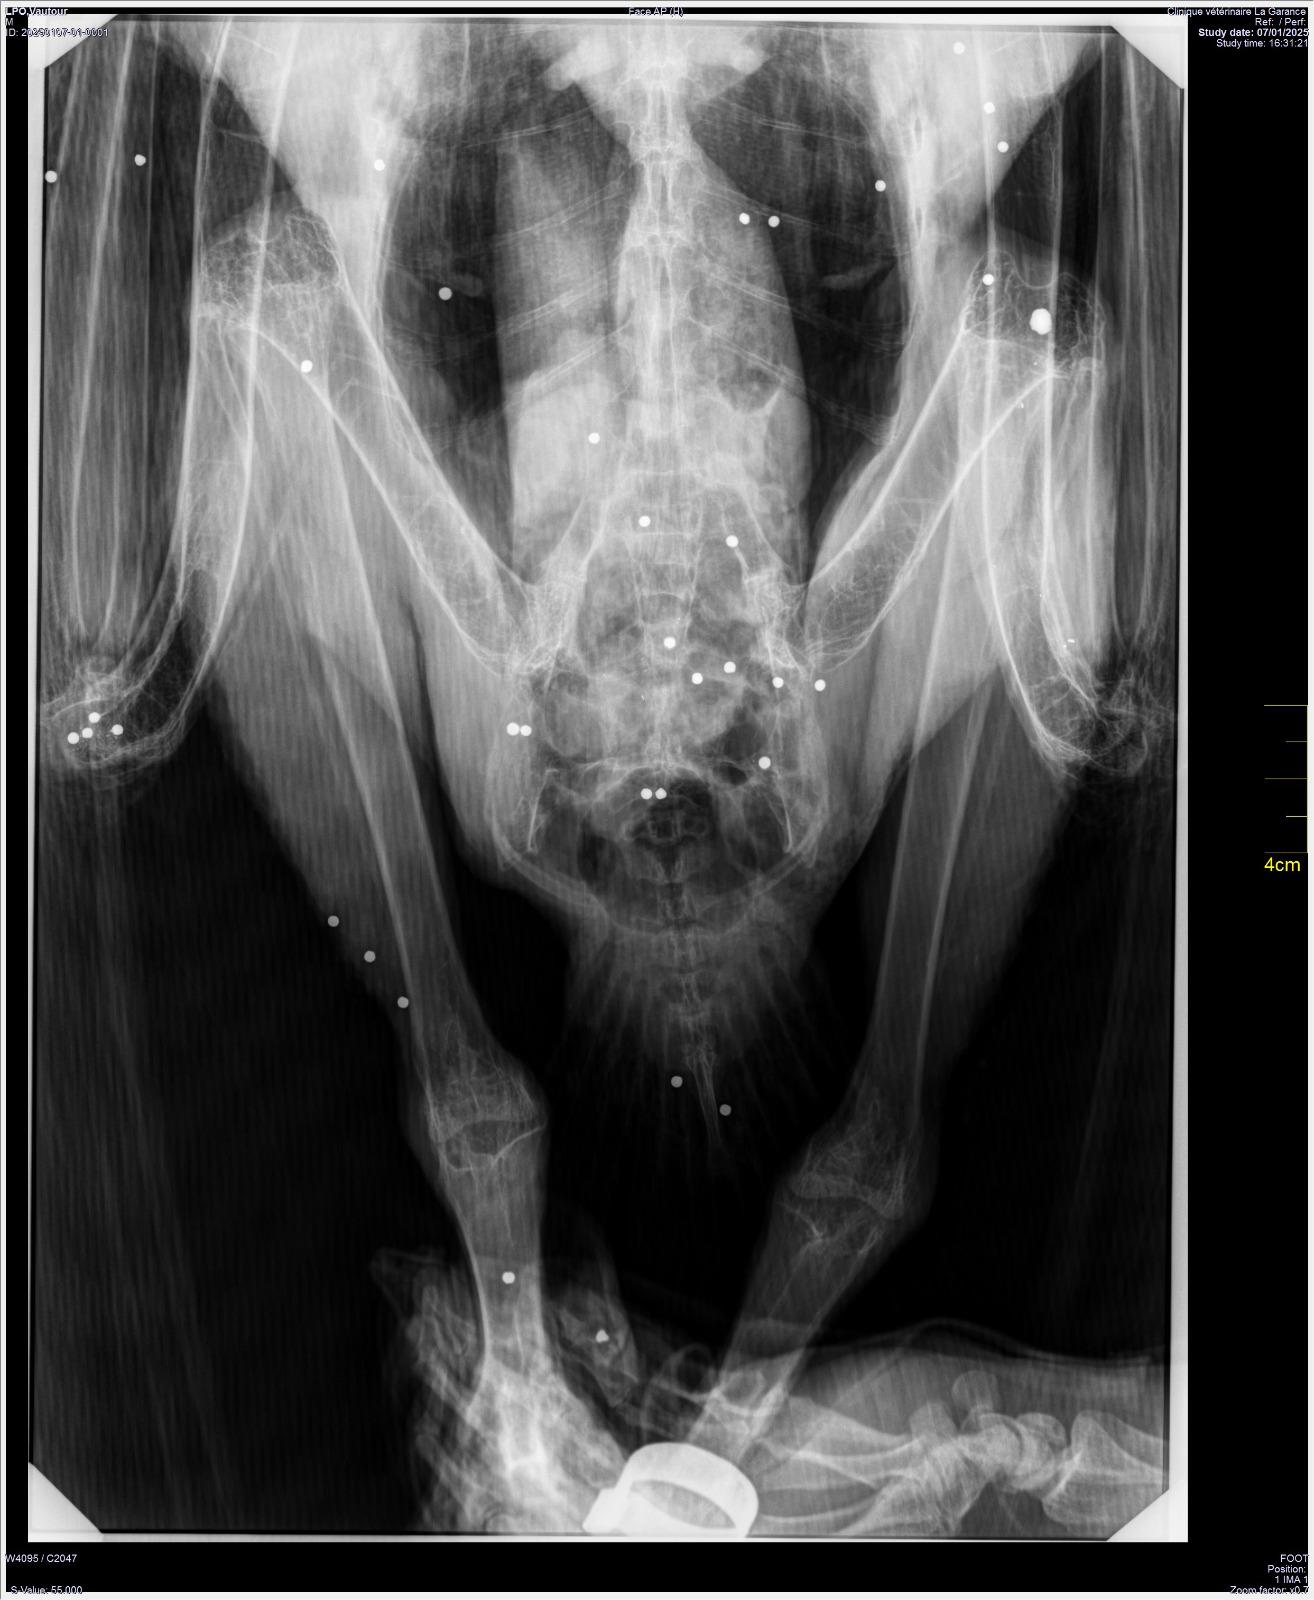

Au début du mois de janvier, nous avons accueilli un Vautour moine en détresse, une espèce très menacée en France. Trouvé gisant au bord d’une rivière dans les Alpes de Haute Provence, le grand rapace est arrivé extrêmement affaibli au Centre de sauvegarde. Victime d’une importante hémorragie interne, il ne pouvait pas prendre appui sur sa patte gauche et avait un œil injecté de sang. Une radiographie a révélé la cause de ces maux, mais aussi la gravité de son état : son corps était criblé de plombs. Aucune partie n’avait été épargnée : tête, ailes, corps, pattes. Au total plus d’une soixantaine de plombs, ce qui laisse supposer un tir à proximité.

ILD est restée en soins intensifs pendant plusieurs semaines. Elle a subi une opération pour lui retirer le plus gros plomb dans l’aile, réalisée par le Dr Frank Dupraz, notre vétérinaire référent, qui nous a aussi fourni des conseils tout au long de sa convalescence et que nous remercions chaleureusement.